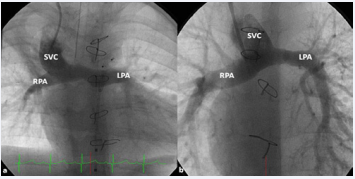

Figure 27 Selected cine frames in postero–anterior (a) and sitting up (b) views, demonstrating bidirectional Glenn procedure (the superior vena cava [SVC] is anastomosed with the right pulmonary artery [RPA]) in two different patients during Stage II of Fontan procedure. Unobstructed flow from the SVC to the right (RPA) and left (LPA) pulmonary arteries is shown [82].

Figure 27: Selected cine frames in postero–anterior (a) and sitting up (b) views, demonstrating bidirectional Glenn procedure (the superior vena cava [SVC] is anastomosed with the right pulmonary artery [RPA]) in two different patients during Stage II of Fontan procedure. Unobstructed flow from the SVC to the right (RPA) and left (LPA) pulmonary arteries is shown [82].Figure 28 Selected cineangiographic frames showing a bilateral bidirectional Glenn procedure (Stage II). In a, an injection into the superior vena cava (SVC) shows prompt opacification of the right pulmonary artery (RPA). The arrow in a points to the unopacified blood from a persistent left superior vena cava (PLSVC). In b, an injection into the PLSVC shows prompt opacification of the left pulmonary artery (LPA). The arrow in b points to the unopacified blood from the right SVC. Note the unobstructed flow from the respective SVCs into the pulmonary arteries [82].

Figure 28: Selected cineangiographic frames showing a bilateral bidirectional Glenn procedure (Stage II). In a, an injection into the superior vena cava (SVC) shows prompt opacification of the right pulmonary artery (RPA). The arrow in a points to the unopacified blood from a persistent left superior vena cava (PLSVC). In b, an injection into the PLSVC shows prompt opacification of the left pulmonary artery (LPA). The arrow in b points to the unopacified blood from the right SVC. Note the unobstructed flow from the respective SVCs into the pulmonary arteries [82].